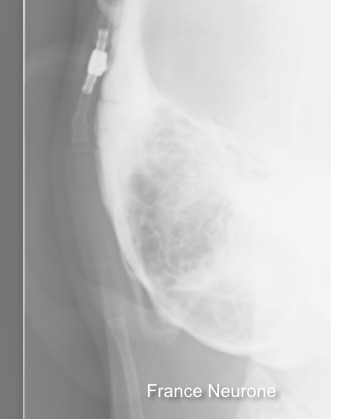

il existe un grand nombre de valves ; il n’est pas toujours aisé de les reconnaitre radiologiquement. voici la liste des plus courantes :

comment reconnaitre radiologiquement le type de valve ?